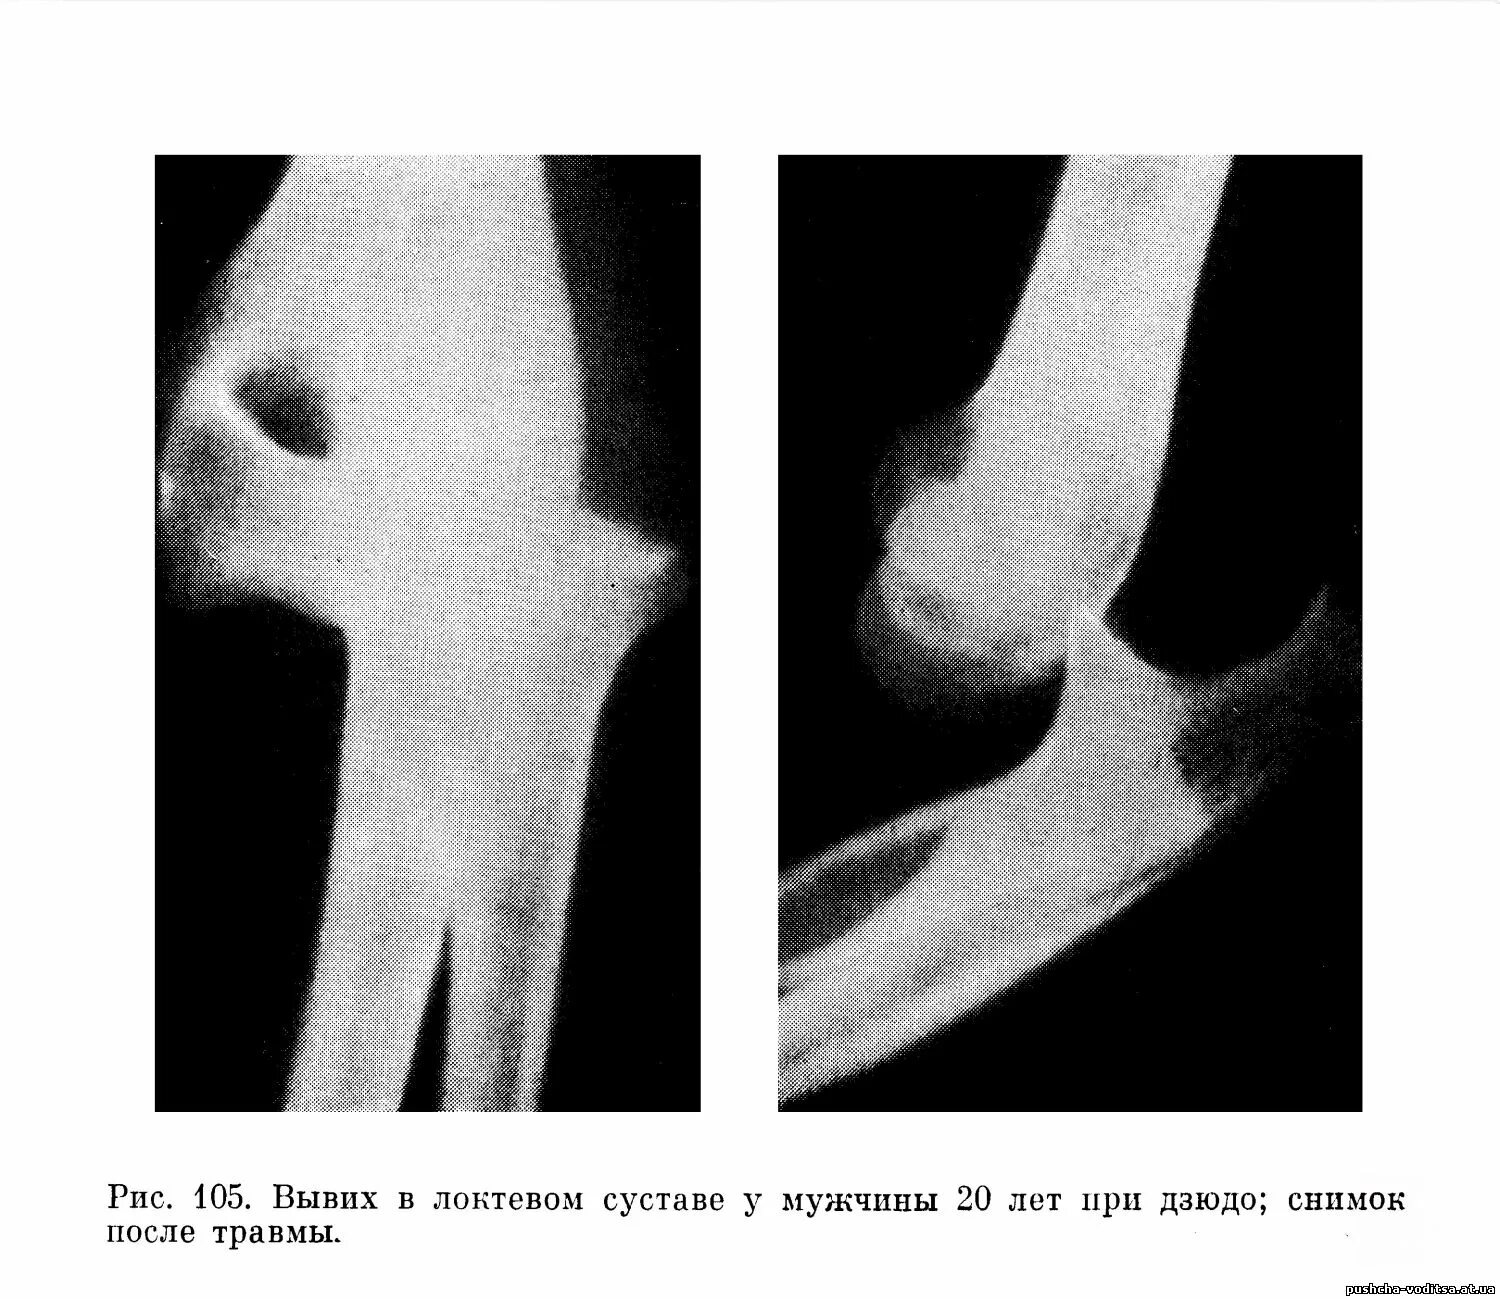

Задний вывих локтевого сустава.

Вывих локтевого сустава рентген. вывих локтевого сустава рентгенограмма. травматический вывих локтевого сустава.